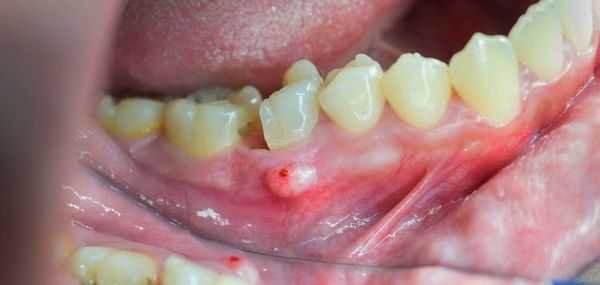

о Формирование свищк с гнойным отделяемым

После острой стадии наступает подострая. На десне образуется гнойничок или свищ, через который гнойные выделения и воспалительная жидкость выходят наружу.

При переходе острого остеомиелита в хронический состояние пациента улучшается. Боли уменьшаются, становятся ноющими. Формируются свищевые ходы, которые могут выглядеть, как сложная система каналов и выходить на поверхность кожи далеко от места повреждения. Из свищей выделяется умеренное количество гнойного отделяемого.